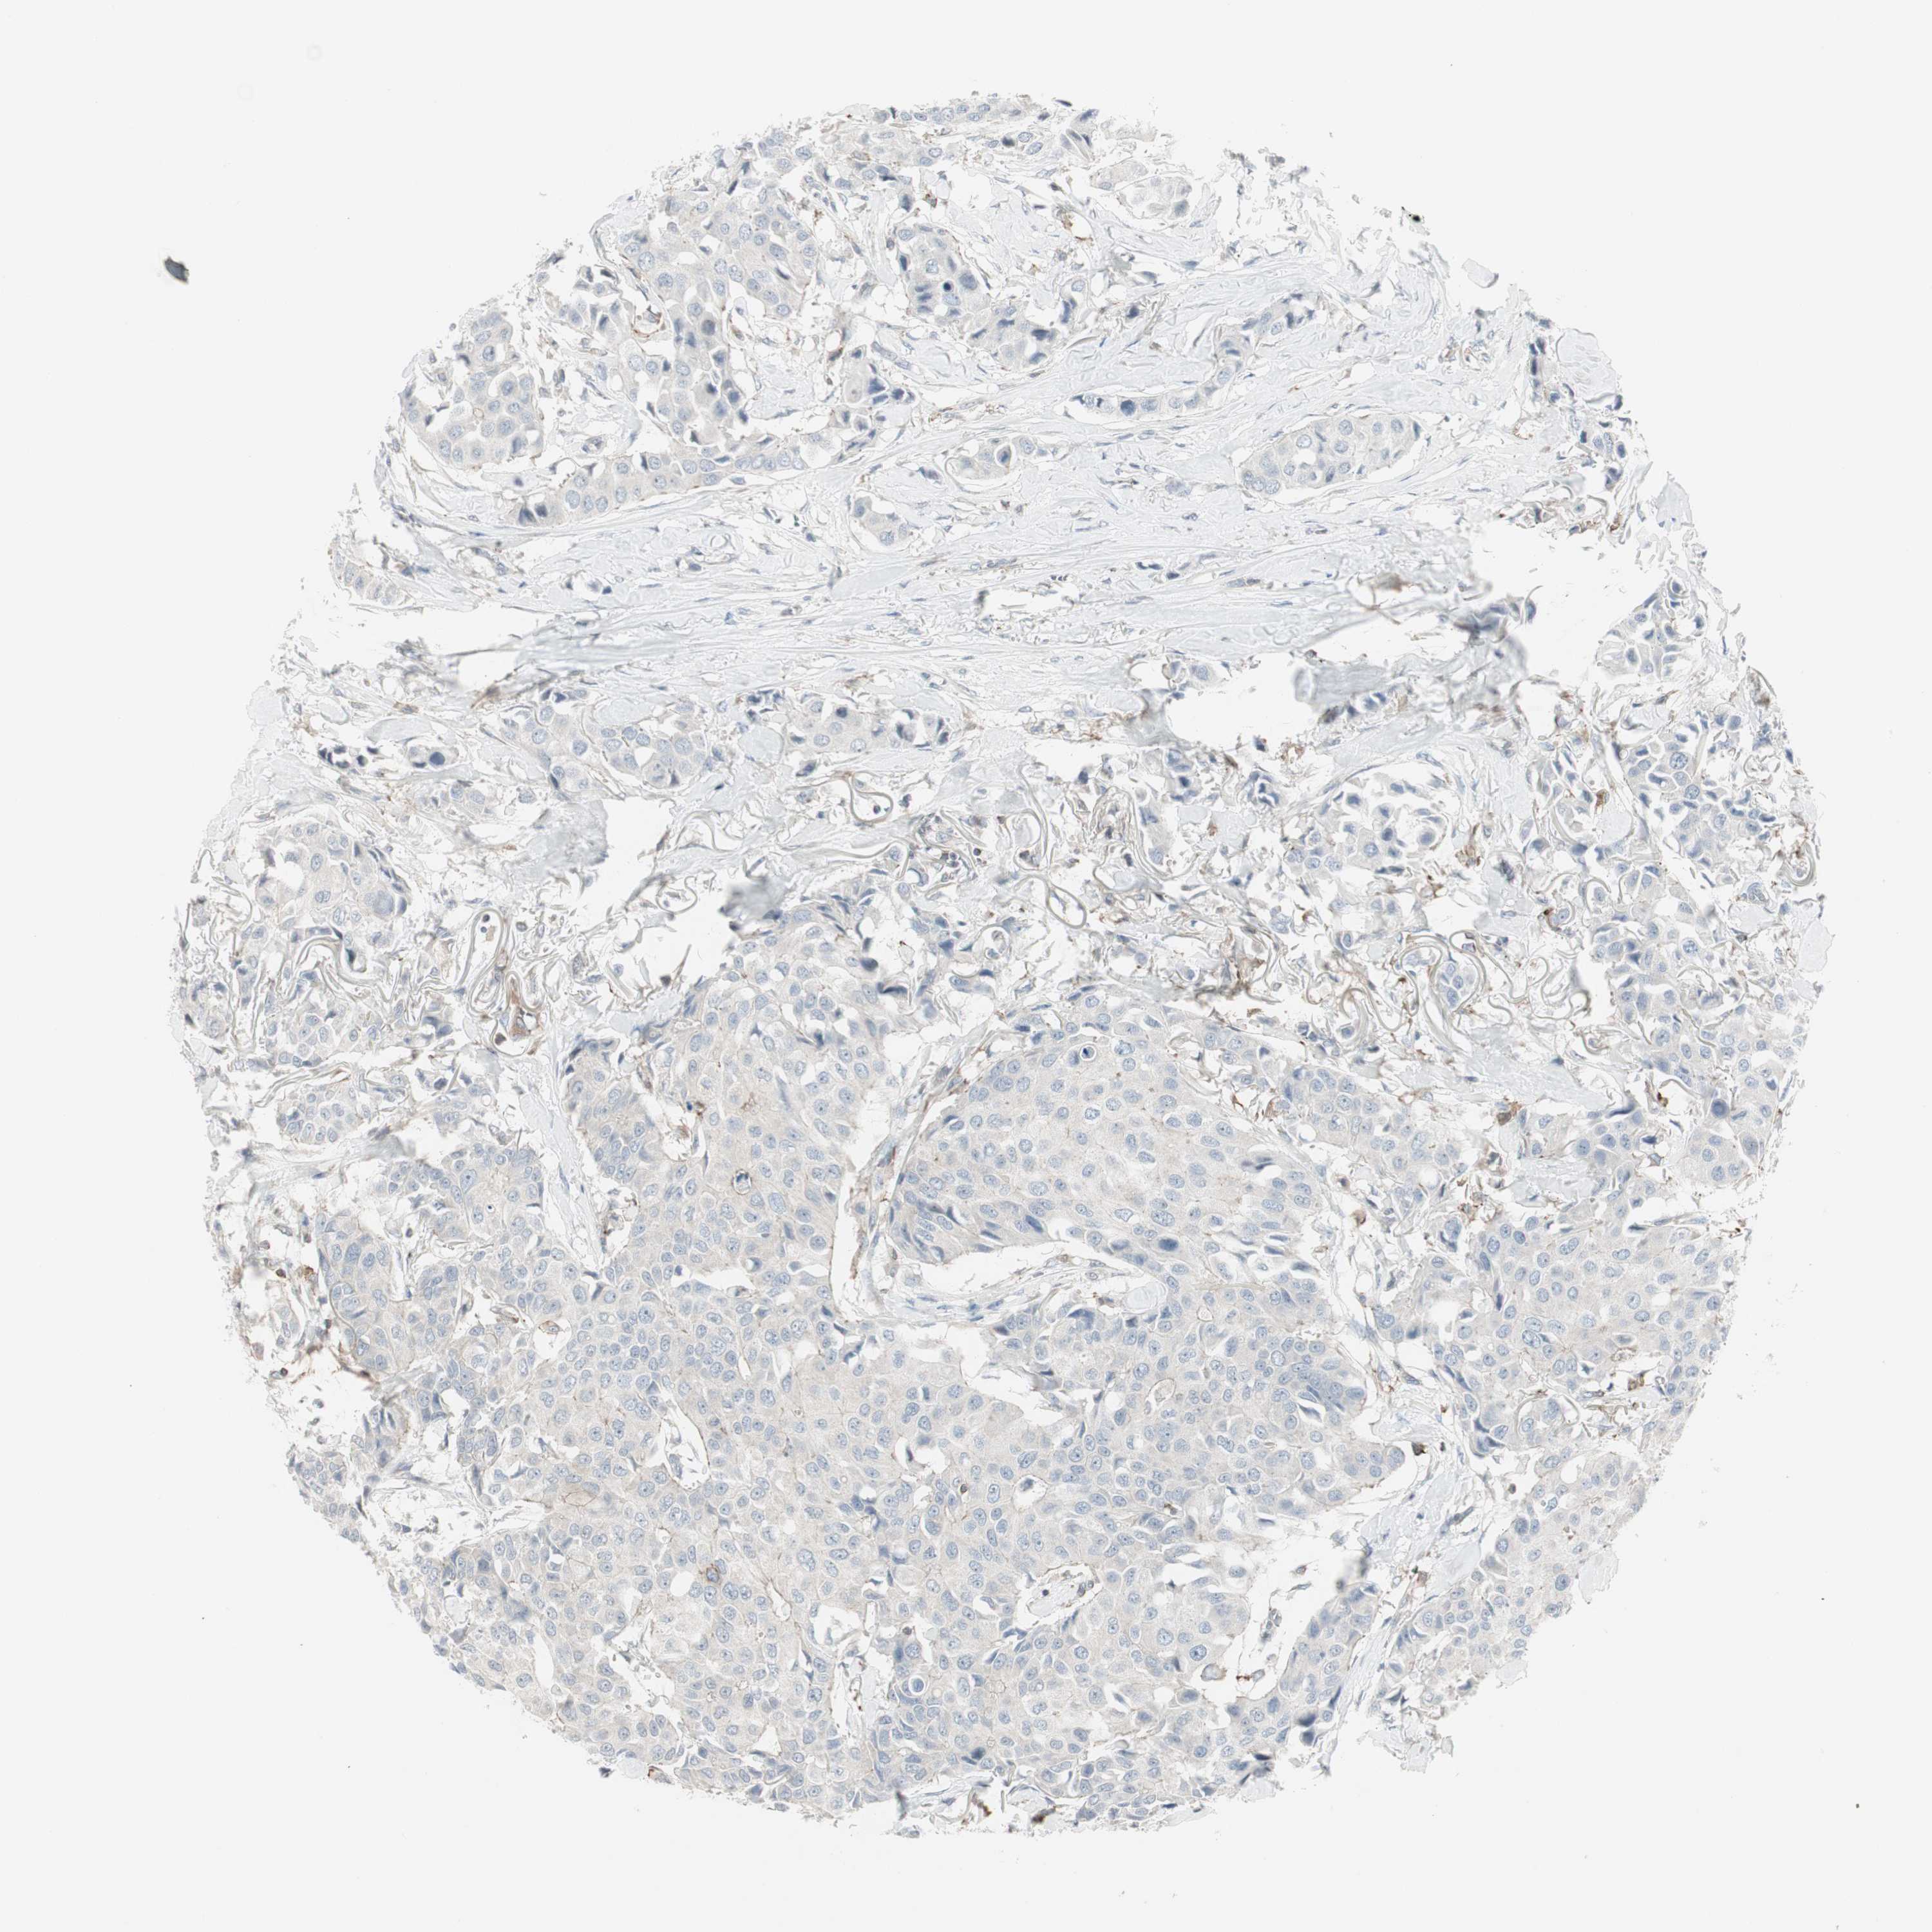

CANCER BREAST CANCER Show tissue menu

BRCA TCGA BRCA VALIDATION PROTEIN EXPRESSION